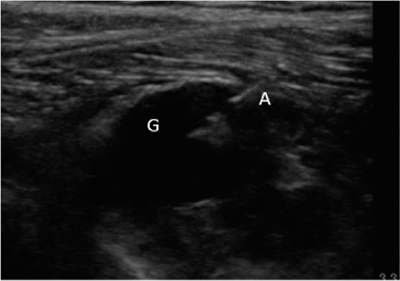

Se diagnosticó, por lo tanto, paresia de nervio peroneo derecho secundario a compresión por ganglión de articulación tibio-peronea proximal y se propuso al paciente un manejo intervencionista del mismo, que aceptó. Se realizó drenaje ecoguiado empleando una sonda lineal de alta frecuencia (10-5 MHz), una aguja de 20 G y una jeringa roscada de 5 ml (Figura 2), retirándose sin dificultad 1,5-2 ml de contenido mucinoso compatible con ganglión. Posteriormente se realizó infiltración de 1 ml de triamcinolona 40 mg ml diluida en 0,5 ml de mepivacaína al 2 %. Tras el procedimiento se evidencia una clara disminución del tamaño del ganglión.

Fig. 2. Ecografía en corte longitudinal de aspiración con aguja ecoguiada del ganglión. G: ganglión. A: aguja en interior de ganglión iniciando aspirado.